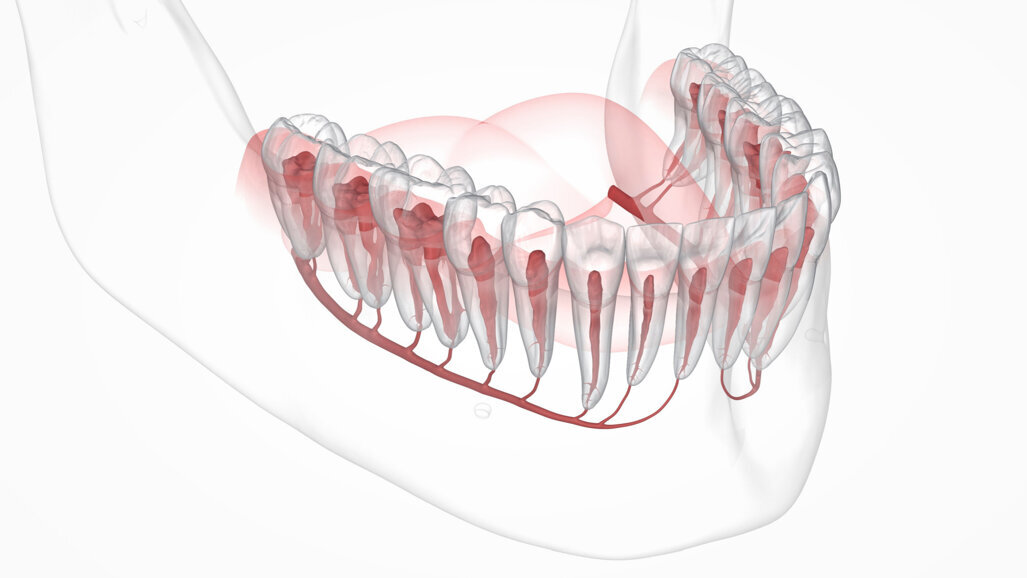

Researchers in Finland have created an artificial intelligence-based model that locates the mandibular canals quickly and precisely. (Image: Alex Mit/Shutterstock)

ESPOO/HELSINKI/TAMPERE, Finland: Studies have shown that artificial intelligence (AI) can recognise structural patterns in medical imaging data. However, in dental and maxillofacial radiology, only a few studies have used AI to locate mandibular canals. Knowing their exact location is a prerequisite for dental implant planning. Until now, dental professionals have had to examine radiographs to locate the mandibular canal, a potentially complex and time-intensive process. A recent study from Finland has now tested the use of an AI-based model for this purpose and found that it locates canals in 3D radiographs quickly and precisely.

Localisation of the canal in CBCT images is complicated by anatomical variations in the course and shape of the canal according to individual and ethnicity. To avoid compression or other surgical complications, a safety margin of 2 mm above the mandibular canal is recommended in implantology. Precise knowledge of canal position is also important for various other oral and maxillofacial surgical procedures, such as jaw surgery or removal of third molars.